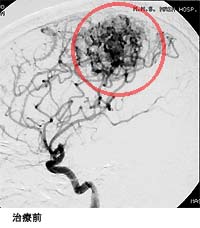

脳出血による半身麻痺と意識障害で発症した患者さんの治療前後の血管撮影を下に示します。(赤線内が脳動静脈奇形の部分)